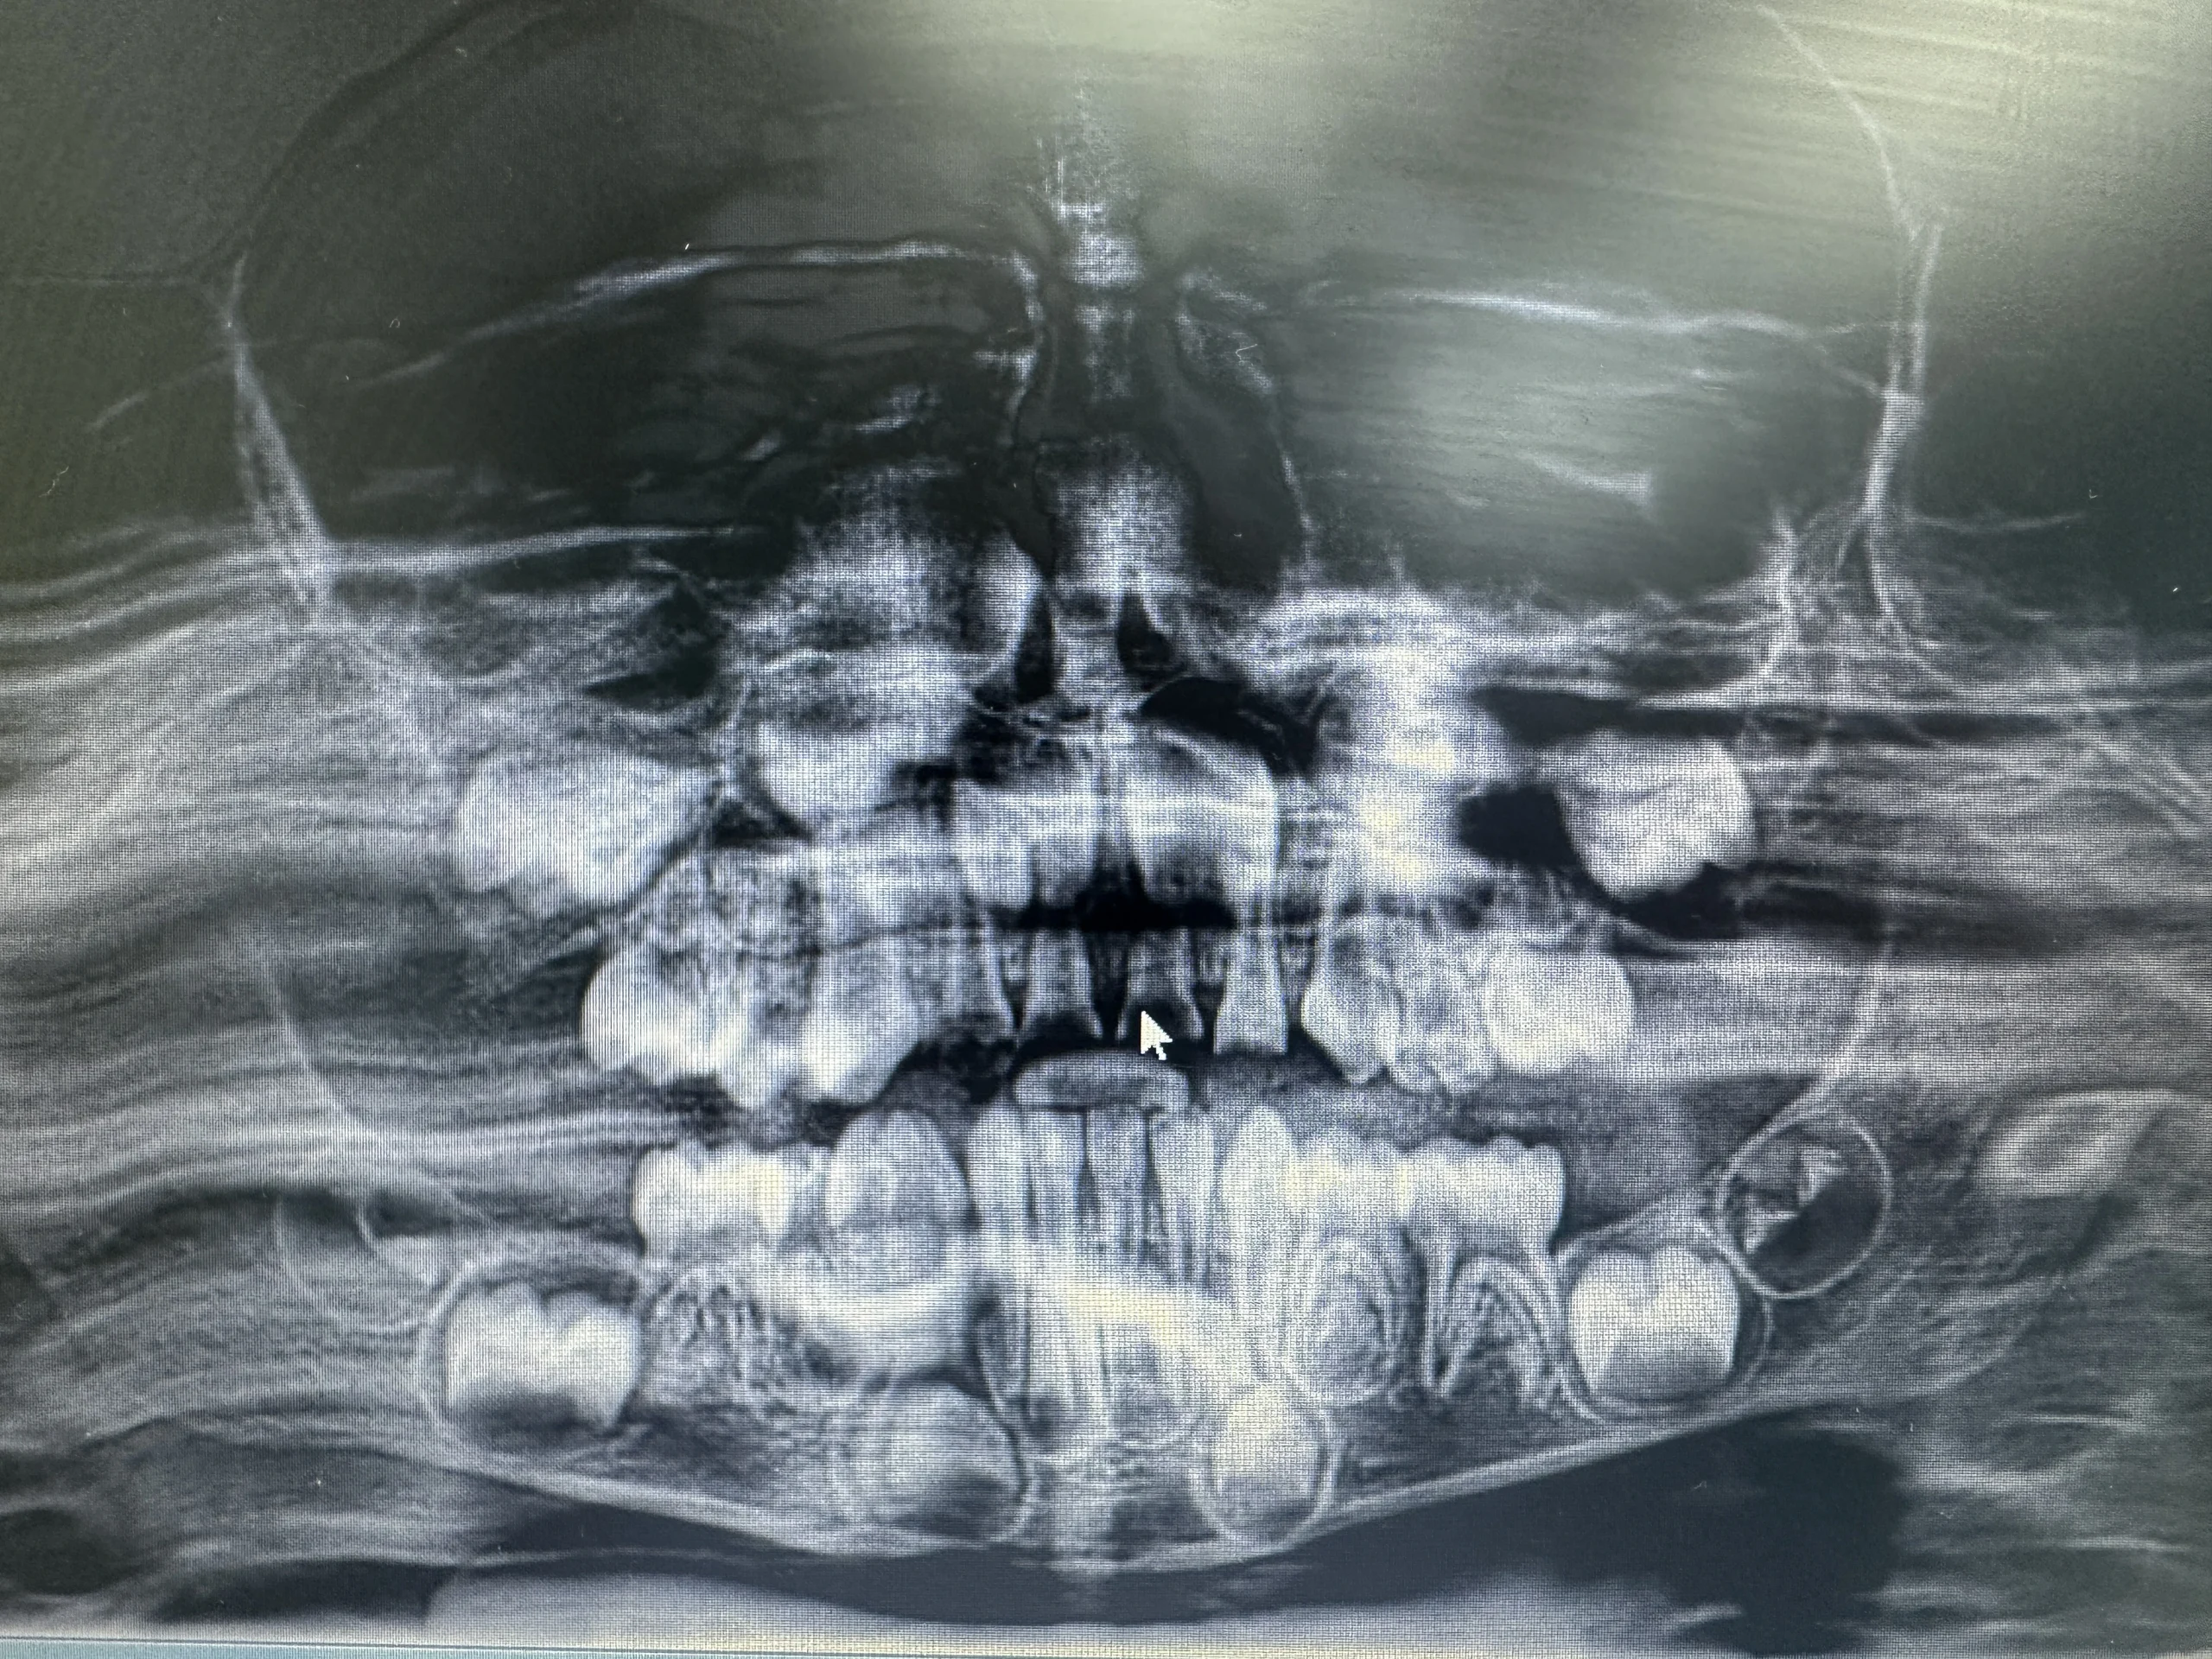

Gross examination showed severely decayed upper primary incisors (#E, #F) with extreme carious lesions in the pulp. Radiographic inspection revealed a pulpal lesion, which was irreversible pulpitis. During examination and treatment, his vital signs were normal.

Diagnosis: Irreversible pulpitis of the primary upper anterior teeth (#E, #F).